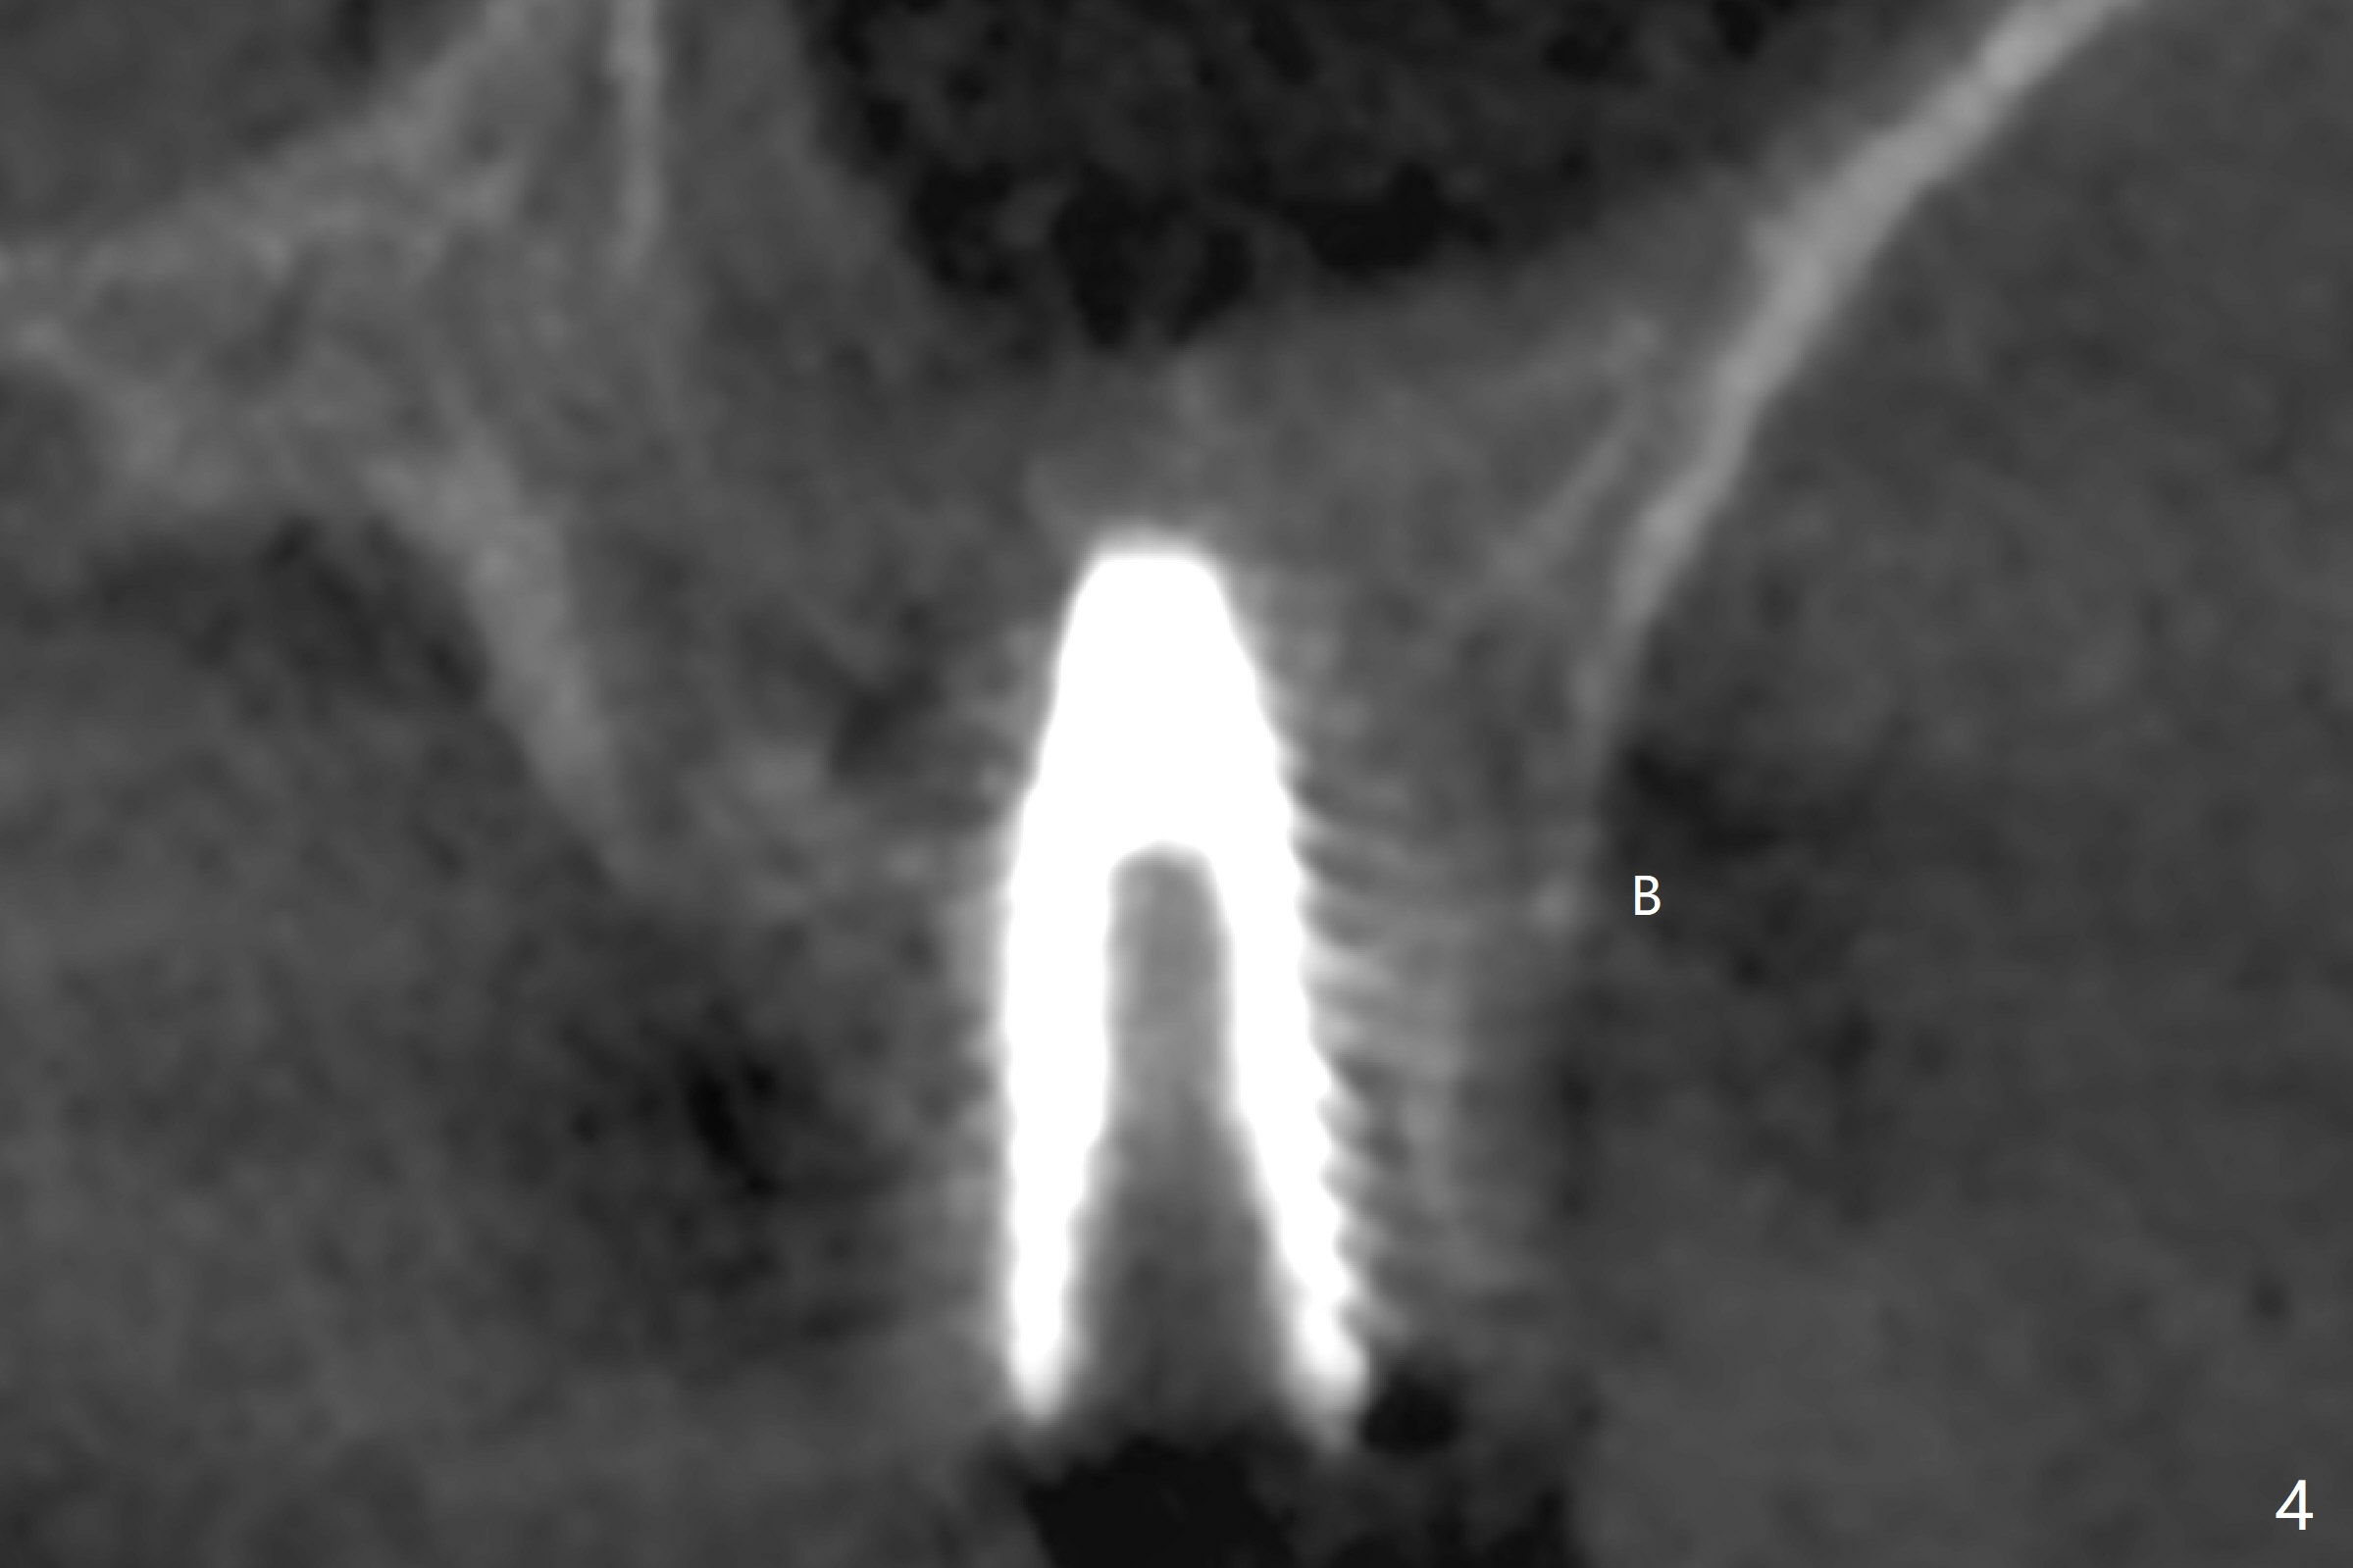

Four and a half months post implant removal, the patient returns for #14 implant placement. To increase bone density, bone expanders are used through the metal sleeve of the previous guide after use of 2.2x7.5 mm drill with 3 O-rings (1 mm shorter than previously designed; Fig.1). The osteotomy continues to form by bone expanders until 2.4/3.7 mm, followed by a 4x10 mm dummy implant (Fig.2-4). Finally a 4.5x7.3 mm implant is placed with ~ 25 Ncm with simultaneous sinus lift (Fig.5). There is no postop nasal hemorrhage. The implant dislodges with the healing abutment 2 months postop. The patient will return for follow up 3 months post 2nd loss. We are going to try again with PRF, UF guided sinus lift kit, sinus expander kit. After implant placement, use the implant at #13 and abutments at #13 and 14 to fabricate splinted provisional to hole the newly placed implant in place. Take preop PA and possible CT. In fact CT and impression are retaken for a new guide.